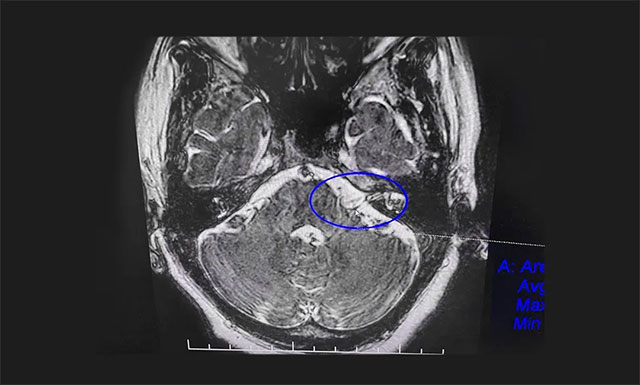

▲ 患者左側(cè)面神經(jīng)根與小血管關(guān)系密切

患者范阿姨入院后,面神經(jīng)MRTA平掃+增強(qiáng)檢查顯示,患者左側(cè)面神經(jīng)顱內(nèi)段根部與周圍小血管關(guān)系密切。沈建康教授團(tuán)隊對患者病情及影像學(xué)資料進(jìn)行充分評估后認(rèn)為,患者藥物治療效果不佳,癥狀反復(fù)發(fā)作,已影響日常生活,有手術(shù)指征,未見明顯手術(shù)禁忌癥。在告知患者及家屬手術(shù)風(fēng)險后,沈教授團(tuán)隊為患者開展了面神經(jīng)微血管減壓手術(shù)。